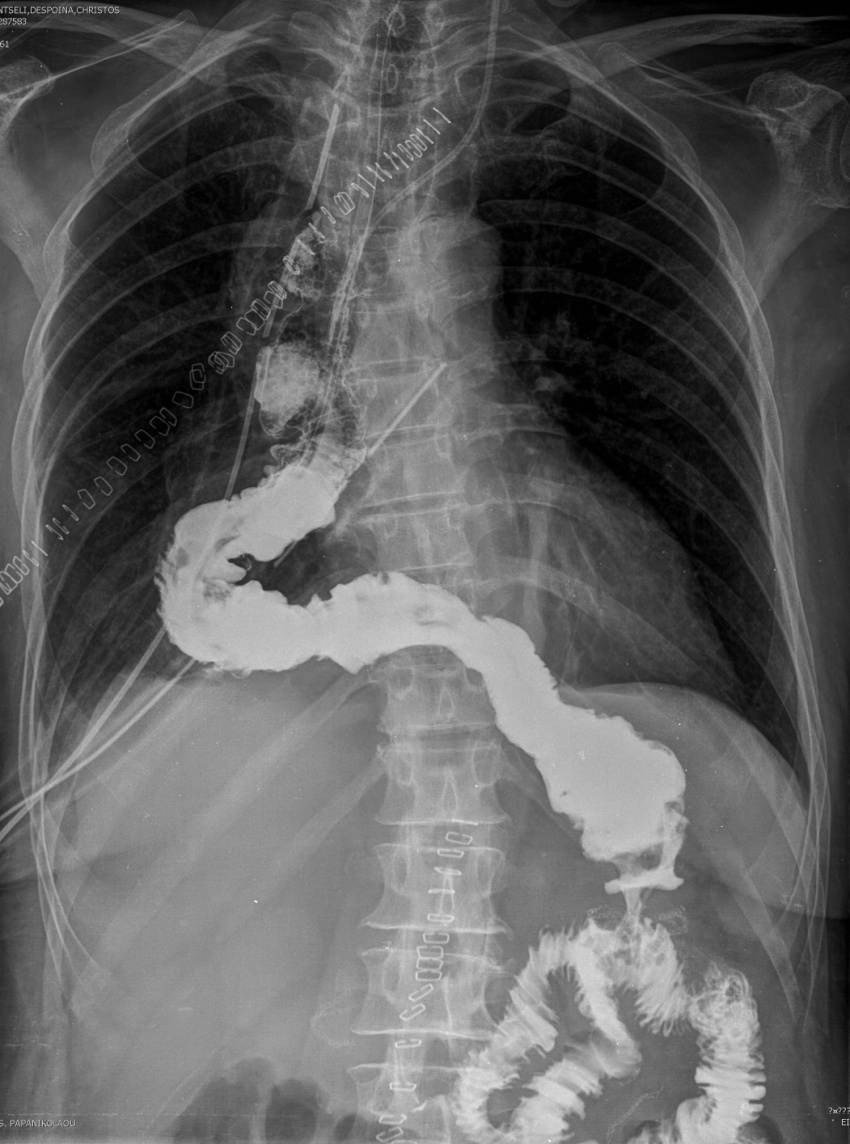

Gastrografin swallow - Colonojejunal anastomosis following esophagogastrectomy for extensive esophageal and gastric burns (Courtesy Dr. V. Penopoulos)